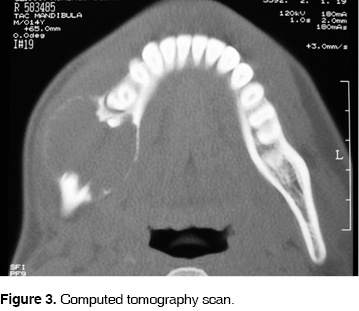

A 14 year old boy was admitted to the dental clinic at the Hospital Juárez de México in July 2004, with a right mandibular tumor like lesion, of apparently 7 months of evolution. The patient reported tenderness and there was no other relevant history for this lesion. The swelling was located from the right second premolar to the third molar zone with vestibular expansion with displacement and mobility of the first and second molar ipsilateral (Figure 1). The panoramic radiograph showed a unilocular radiolucid lesion that extended from the first and second right molars with a very close relation to the third molar, well defined borders and measuring approximately 30 x 20 mm, producing displacement of the teeth involved (Figure 2). The simple CT scan showed a lesion that produced vestibular and lingual cortical slimming and expansion with preservation of the mandibular border (Figure 3).